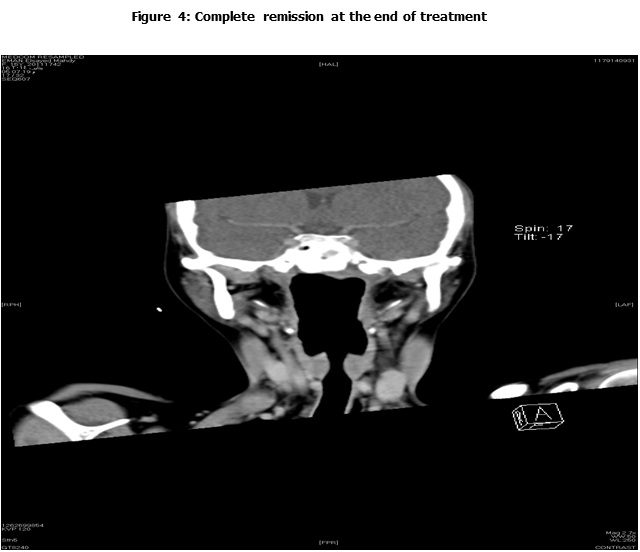

This is a retrospective study including all the newly diagnosed pediatric NPC who were diagnosed and treated at the Children Cancer Hospital Egypt (CCHE) during the period from July 2007 to December 2012. All imaging studies (e.g., CT or MRI scans) were reviewed by a senior head and neck radiologist for proper staging and assessment of tumor response. Patients were staged according to AJCC staging system. Modified version of the Response Evaluation Criteria in Solid Tumor (RECIST) was used to assess response.

This is a retrospective study including all newly diagnosed pediatric NPC at Children Cancer Hospital Egypt CCHE during the time period from July 2007 to December 2012. The patients' profiles were systematically reviewed for characteristics including pathology, laboratory, radiological work up and documented toxicities. All imaging studies (e.g., CT and MRI scans) were reviewed by a senior head and neck radiologist for proper staging and assessment of tumor response.

Pretreatment evaluation included a complete history and physical examination, complete blood count, serum biochemistry tests (including evaluation of electrolyte levels, hepatic and renal function tests), CT or MRI scans of the head and neck region, chest and bone scan. During therapy weekly examinations and laboratory evaluations were performed. Tumor response was assessed by clinical examination with appropriate MRI imaging studies after completion of neoadjuvant chemotherapy and at the end of radiotherapy.

Complete Response (CR): complete disappearance of the tumor confirmed.